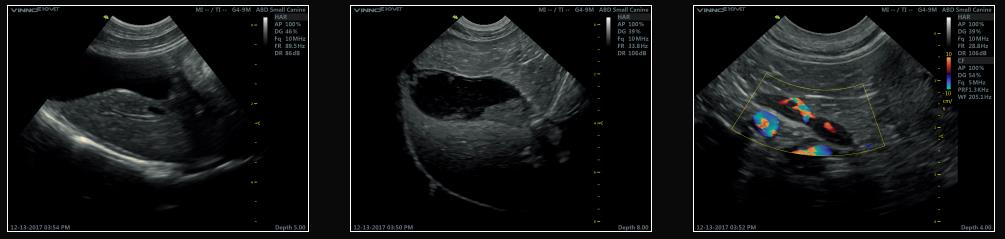

VINNO E10 VET

Ultrasonograf weterynaryjny z zaawansowaną technologią.

• stacjonarny, dopplerowski ultrasonograf weterynaryjny do wielu zastosowań klinicznych

• szeroki wybór głowic obrazowych

• 10-calowy panel do wygodnego zarządzania dostępnymi funkcjonalnościami

• Innowacyjna platforma RF – przetwarzanie sygnału RF w celu uzyskania lepszej rozdzielczości i definicji

• szerokie możliwości post processingu obrazów, również w trybie Dopplera

Stacjonarny ultrasonograf weterynaryjny VINNO E10 VET to doskonałe rozwiązanie dla klinik ceniących sobie dobrą jakość. Weterynaryjny aparat USG pozwala na badanie zarówno dużych, jak i małych (w tym egzotycznych) zwierząt. System został zbudowany w taki sposób, by praca z nim była jak najwygodniejsza. Ultrasonograf weterynaryjny posiada duży, 19 calowy ekran, panel dotykowy do sterowania, pulpit sterowniczy z jasno opisanymi funkcjonalnościami pozwalają na szybką i skuteczną pracę.

Wysoka jakość obrazu

Rozwiązania zastosowane przez producenta ultrasonografów marki VINNO VET to funkcja wyróżniająca te urządzenia wśród konkurencji. Wykorzystane algorytmy pozwalają na jakość obrazu nie spotykaną w podobnych aparatach USG tej klasy. Możliwe jest to dzięki Platformie RF, standardowo dostępnej w ultrasonografach weterynaryjnych tej marki.

Ultrasonograf weterynaryjny VINNO E10 VET – dane techniczne:

• 18.5-calowy monitor LED, który dostarcza obraz najwyższej jakości

• 10-calowy, inteligentny panel do wygodnego zarządzania dostępnymi funkcjonalnościami

• Innowacyjna platforma RF

• Doppler fali pulsacyjnej PW oraz wielobramkowy Doppler fali pulsacyjnej HPRF

• Automatyczne śledzenie PW/CW

• Obrazowanie harmoniczne z odwróceniem fazy

• VFusion (obrazowanie wielokierunkowe); VSpeckle (redukcja artefaktów, wyostrzenie obrazu)

• Obrazowanie trapezoidalne

• Obrazowanie w trybach: Color, Power, Directional Doppler

• SGC (Scanning Gain Compensation)

• Powiększenie obrazu/wyświetlenie w trybie pełnego ekranu

• Obrazowanie 3D/4D